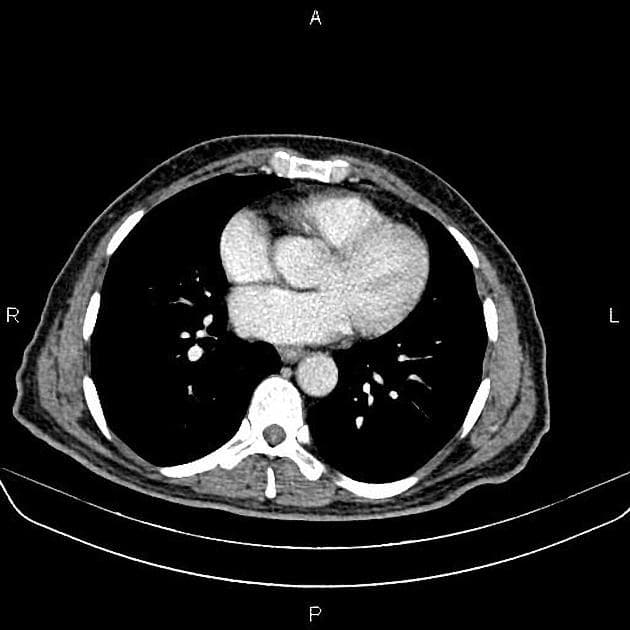

Axial C+ portal venous phase

Ca bệnhÁp xe gan kèm rối loạn tưới máu gan

Áp xe gan kèm rối loạn tưới máu gan

- GAN to (hepatomegaly) kèm gan nhiễm mỡ (fatty liver).

- Thấy một ổ tổ chức dạng nang - nhiều ngăn - giới hạn không rõ (ill-defined multiseptated multiloculated) ở phân thùy VII/VIII của gan, có tăng quang viền (rim enhancement) ngoại vi, kèm theo một ổ vôi hóa và dấu hiệu "cluster sign". Ổ này chèn ép một phần đoạn gan của tĩnh mạch chủ dưới (inferior vena cava - IVC).

- Rải rác ở cả hai thùy gan thấy một số tổn thương giảm tỷ trọng (hypodense lesions) với kích thước khác nhau.

- Thấy nhiều vùng tăng quang tĩnh mạch (venous enhancement) ở cả hai thùy gan, phân bố cả trung tâm và ngoại vi.

- Không xác định được tĩnh mạch gan trái, giữa và phải (left, middle and right hepatic veins).

- Tĩnh mạch cửa (portal vein) thông thoáng (patent).

- Hình ảnh phù hợp với (consistent with) áp xe gan gây chèn ép một phần tĩnh mạch chủ dưới liền kề và rối loạn tưới máu gan (hepatic perfusion disorders).

- Trong trường hợp này, hình ảnh CT cho thấy rối loạn tưới máu gan, có thể thứ phát do không thấy hình ảnh (non-opacification) hoặc tắc (occlusion) tất cả các tĩnh mạch gan do áp xe gan gây ra.

- Tắc các tĩnh mạch gan có thể dẫn đến tăng áp lực xoang gan (sinusoidal pressure), kéo theo tăng lưu lượng động mạch gan, dẫn đến thông động tĩnh mạch cửa chức năng trong gan (functional intrahepatic arterioportal shunt)¹.

Trường hợp này mô tả một áp xe gan mủ ở phân thùy VII/VIII gây hiệu ứng khối, chèn ép một phần đoạn gan của tĩnh mạch chủ dưới và không thấy hình ảnh các tĩnh mạch gan, dẫn đến rối loạn tưới máu gan. Tắc nghẽn dòng chảy tĩnh mạch này làm tăng áp lực xoang gan, từ đó tăng lưu lượng máu động mạch gan, tạo thành thông động tĩnh mạch cửa chức năng trong gan. Hiện tượng này bắt chước các dị dạng mạch máu và cần phân biệt với các bệnh như giãn mạch máu dạng xuất huyết di truyền hoặc hội chứng Budd-Chiari. Đái tháo đường làm tăng nguy cơ áp xe gan, đặc biệt do vi khuẩn gram âm. Dù cấy máu âm tính, chẩn đoán vẫn được xác định dựa trên lâm sàng và hình ảnh. Việc điều trị kháng sinh sớm và theo dõi bằng hình ảnh là rất quan trọng, vì việc bỏ sót theo dõi có thể dẫn đến biến chứng do rối loạn tưới máu kéo dài.